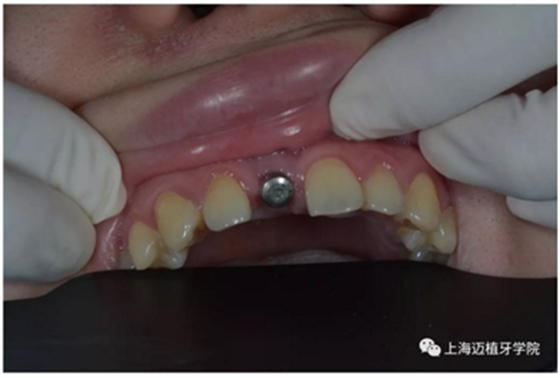

二期手術(shù)

3月后恢復(fù)良好,上愈合基臺(tái)

2周后袖口成形